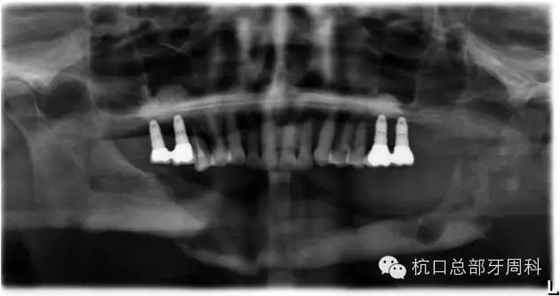

全景片:大范圍火山口樣/彈坑樣骨缺損

CT:左下缺牙區(qū)及部分升支存在骨破壞

初診時全景片2011.7